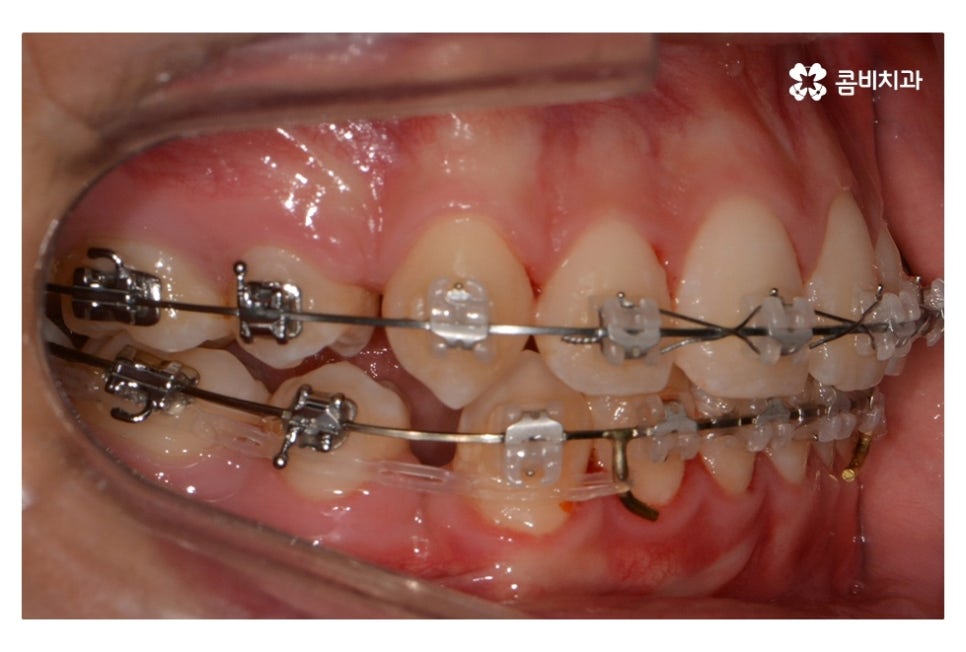

위 사진에서 보시면 시간이 지나면서 발치를 했던 치아의

공간이 사라지고 교정을 통해서 치열이 가지런해진 것을 확인할 수 있는데요.

중학생치아교정에 있어서 중요한 사항이 단지 치열만이

가지런해 보이는 것이 아닌 얼굴과의 조화와 교합이라 할 수 있어요.

보이는 치열뿐 아니라 돌출입으로 고민을 하시는 분들도

적지 않은 만큼 시술 후 결과에 있어서 얼굴 전체와의

조화를 충분히 생각해야 하며 치료 후 결과가 잘 유지되고